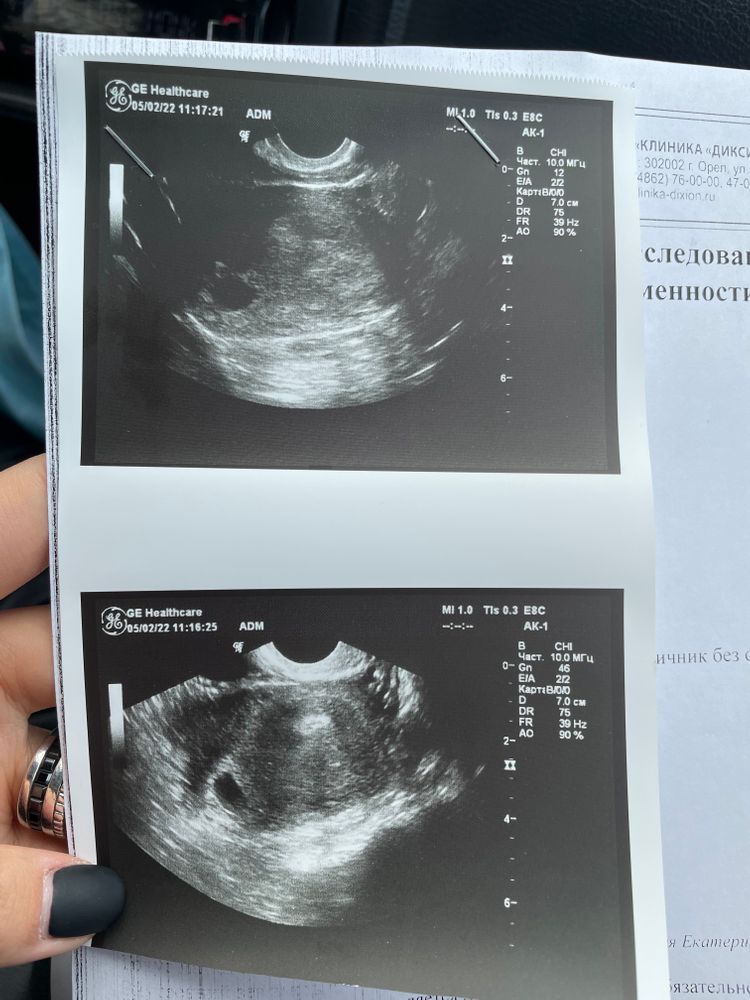

Первое УЗИ

Ну у вас только 5 недели, рано ещё для ЖМ. Через неделю сходите, если не появится то уже стоит напрягаться. А пока рано вы пошли. На узи раньше 7 недель делать вообще нечего

Нормальное узи. Только срок видимо максимально маленький.

Думаю, что вы пошли на УЗИ рано. Первое УЗИ делают ближе к концу седьмой недели